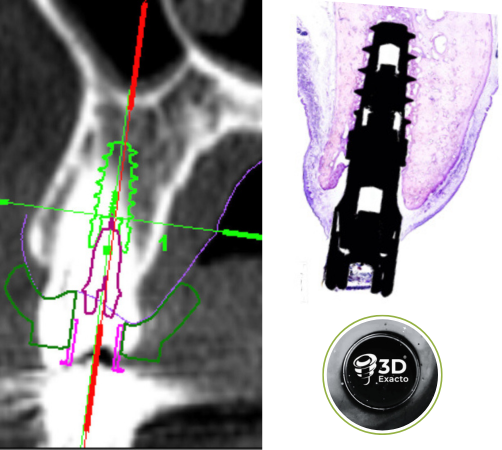

Cirugía Guiada por Ordenador

En nuestra clínica, ofrecemos cirugía guiada utilizando software 3D exacto, una técnica innovadora que nos permite planificar con precisión la colocación de los implantes y asegurar su correcta integración en el hueso maxilar o mandibular. De esta manera, podemos garantizar una colocación precisa, sin errores y con un mínimo de molestias para el paciente.

Durante la cirugía, se utilizan guías quirúrgicas personalizadas basadas en esta planificación digital. Estas guías ayudan a posicionar el implante en el lugar exacto determinado en la planificación, asegurando que esté perfectamente alineado y rodeado de suficiente hueso, lo cual es crucial para su integración y estabilidad a largo plazo. Además, esta precisión garantiza que el implante esté en la posición óptima para recibir la prótesis dental, lo que mejora la funcionalidad y estética del resultado final.